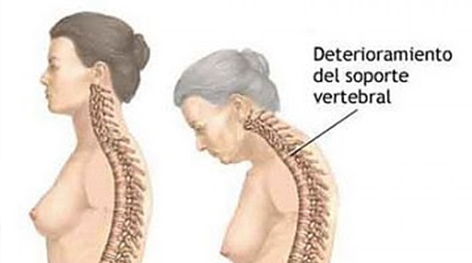

Es una enfermedad caracterizada por la disminución de la densidad de la masa ósea por un defecto en la absorción del calcio; ocasionando una alteración en la calidad del tejido oseo lo que hace que los huesos sean más frágiles incrementando con ello el riesgo de fracturas, especialmente en la cadera, antebrazo, muñeca y columna vertebral.

Las fracturas típicamente osteoporóticas son: la del antebrazo, llamada fractura de Colles, la de vértebra y la de fémur. Pero también pueden producirse otras fracturas como las de húmero proximal, de pelvis y costales. Las fracturas más graves son las de cadera.